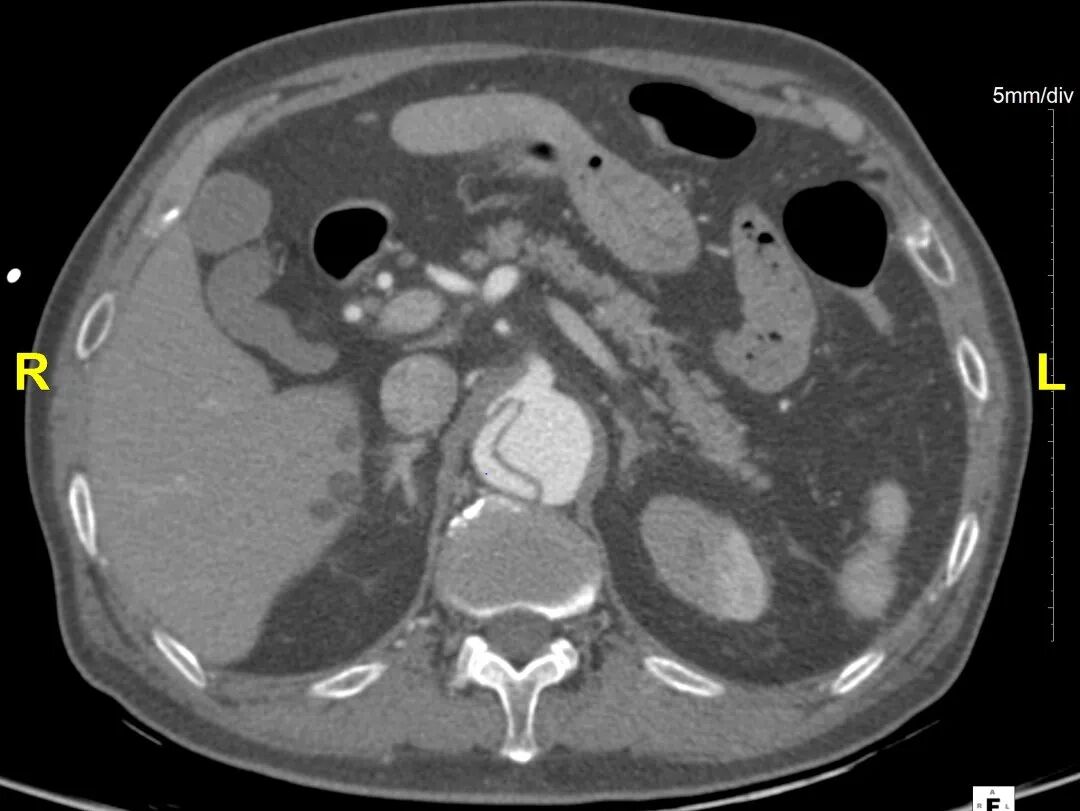

病例CTA详解

横断面影像

1)内膜多处撕裂,真腔严重狭窄。

2)CA假腔供血,SMA双腔供血,LRA假腔供血,RRA真腔供血,腹主段闭塞。

3)LSA起始部平均直径43mm+,降主段多发破口,真腔狭窄。